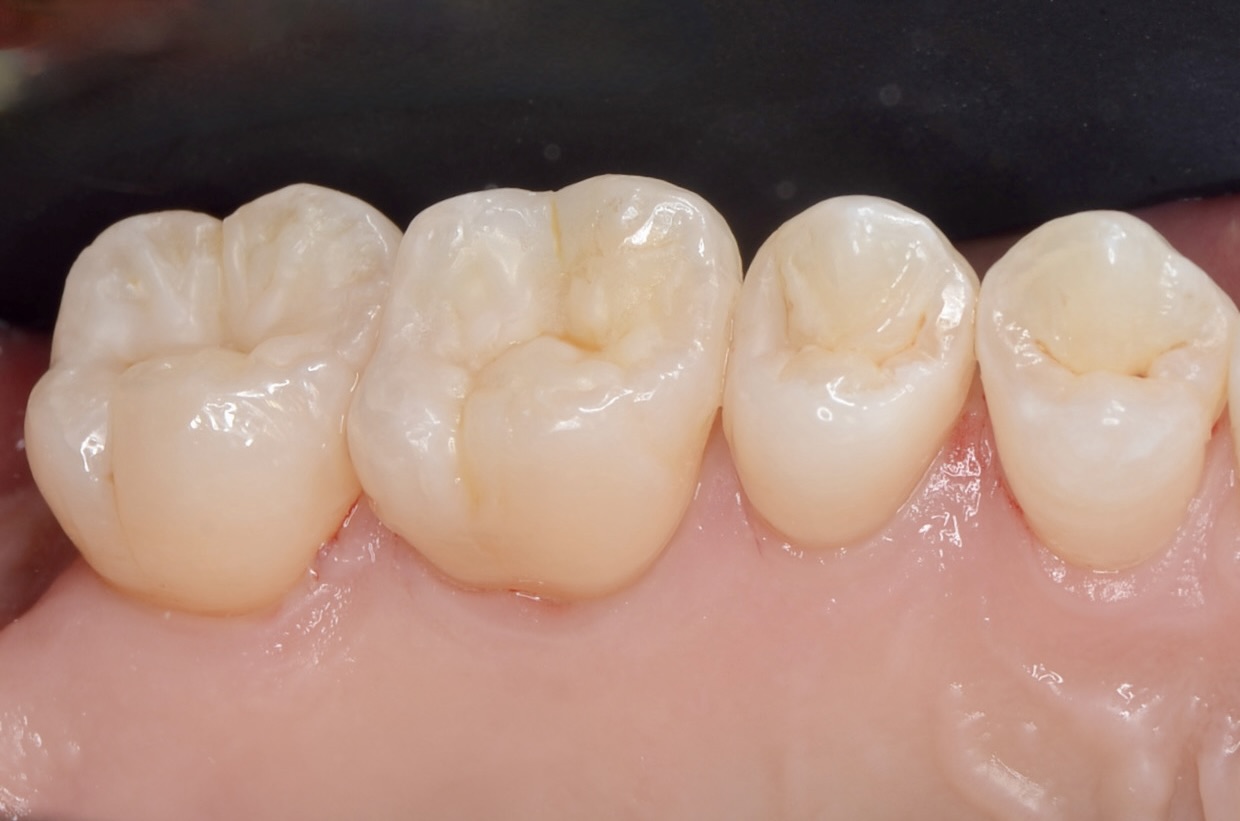

1週間後研磨

歯垢が付きにくいように、歯と歯の間、歯とレジンの境目を丁寧に研磨します。 -

口蓋側よりから見る

滑らかで美しい仕上がりに患者さんも満足されました。 -

頬側よりから見る

ダイレクトボンディングを検討されている方は、こちらのページをご覧ください。